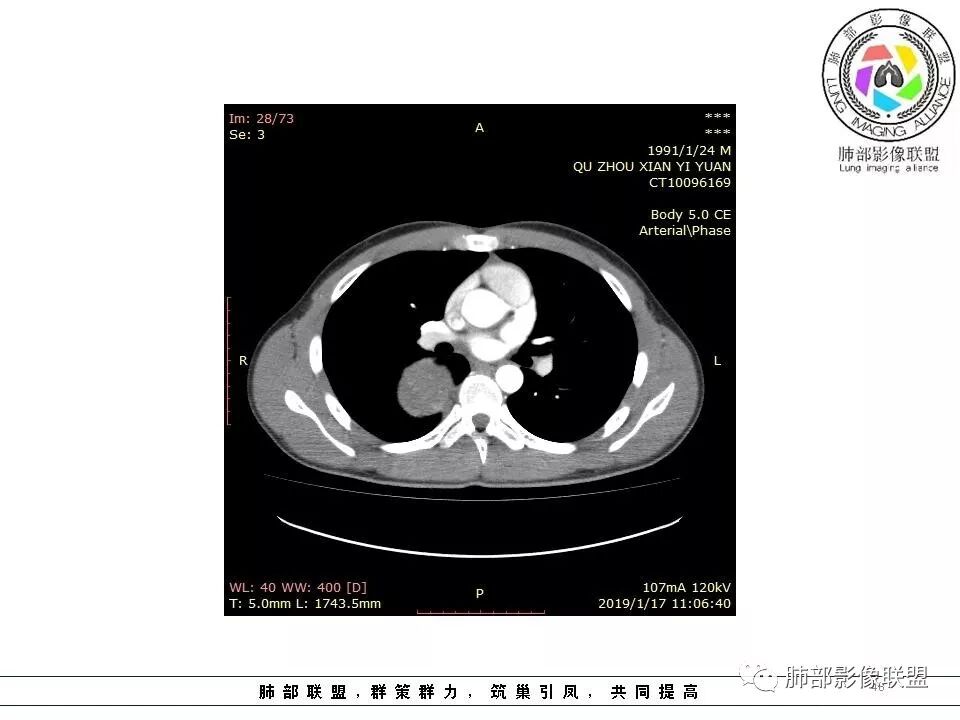

青年男性,间断胸痛;右侧脊柱旁可见一类圆形软组织密度影,密度欠均匀,增强扫描呈轻中度持续强化,邻近肺组织及肺动脉推移,可见肋间动脉供血,部分胸膜下脂肪可见,部分层面似见与右侧椎间孔相连。考虑后纵隔神经源性肿瘤。

青年男性,间断胸痛。右后纵膈脊柱旁软组织占位,形态规则类圆,边缘光整,肺组织受压,D字征,胸膜尾,肋间动脉供血。中度不均匀延迟强化。无支气管进入考虑来源于肺外、肿块与脊柱间未见明显脂肪间隙,考虑来源于胸膜外,考虑神经源性肿瘤,建议穿刺活检。

青年男性,右侧脊柱旁软组织肿块,边缘膨隆,密度不均,临近肺组织受压、胸膜增厚,增强后动脉期呈不均匀强化,并可见肋间动脉供血,延迟期强化较均匀,定位肺外,首先考虑SFT,神经源性肿瘤待排

青年男性,右侧后纵膈肿块,有胸膜尾征,支气管被推压,定位肺外,脏胸膜?血供来自肺动脉及肋间动脉,增强后有强化,蛇纹征,考虑SFT,鉴别鞘瘤

右侧后纵膈肿块,有胸膜尾征,周围肺组织及支气管被推压,定位肺外,脏层胸膜来源,血供来自肺动脉或者支气管动脉,增强后持续渐进强化,蛇纹征,考虑SFT,鉴别鞘瘤。

青年男性,右后上纵隔脊柱旁沟可见团状软组织影,边界清,密度尚均匀,推挤邻近肺组织,胸膜可见掀起,有肺动脉供血,增强轻度蛇皮样强化,纵隔淋巴结未见肿大,邻近骨质未见破坏,胸膜下脂肪间隙消失,考虑SFT孤立性纤维瘤可能性大,鉴别神经鞘瘤,节细胞瘤,建议活检。

青年男性,胸痛,右上纵膈脊柱旁肿块,形态光整规则,支气管被推移,临近的胸膜明显增厚,有胸膜掀起,增强后密度不均匀,可见蛇形血管征,血供似乎有两根血管供血,考虑SFT

1.右上胸内脊柱旁类圆形肿块,质地似乎比较坚实,密度稍显不均,但未显示明确的坏死。

3.相邻椎间孔未见扩大,也未见块影延入椎管,易起自于神经根的鞘瘤似乎找不到支持点。

可惜未提供矢状位骨窗图像,如在肋骨内下缘观察到压迹有助于肋间神经的鞘瘤的判断,这是因为二者之间密切的毗邻关系。

4.静脉期轻度不均匀强化,注意不是环形强化,亦未见明确的“AB区”,这点也不支持神经鞘瘤。临床及病灶轻度强化都不支持副节瘤。

尽管神经纤维瘤的诊断确实有些出乎意外,但病例开阔了我们的视野。